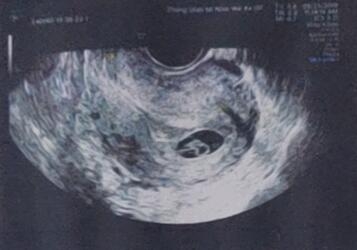

调理好内膜,移植前准备就绪。2022年11月,复苏冷冻移植一枚优质囊胚。秦女士在等待验孕的那段日子也会有不安的情绪,不过努力的付出终是值得的,一次抽血验孕就迎来好孕消息,并顺利通过三超“毕业”。